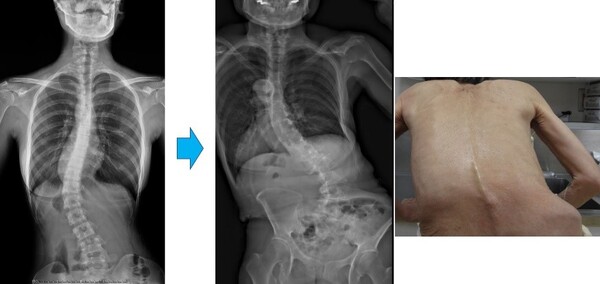

当然ですが手術治療により曲がった背骨は相当真っすぐになり、体幹の捻じれや背中のコブ(出っ張り)も改善します。おおよそ10日間程度の入院が必要になります。毎週火曜日と木曜日に側弯・脊柱変形外来を開設しています。側弯・背骨の変形についてお困りの方は是非一度お気軽にご相談下さい。紹介状などなくても受診できます。(側弯・脊柱変形外来はこちら)

早期に判明した場合や、進行のゆるやかな場合は、装具による進行を予防します。弯曲の程度や、脊柱の捻れが大きい場合には手術による矯正の適応となります。なぜならば、弯曲の大きい側弯は成長終了後も毎年僅かずつ進行し、将来的に高度の変性側弯症になってしまうからです。